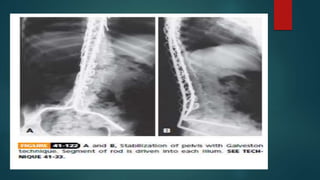

 GALVESTON SACROPELVIC FIXATION:

 Another popular method for achieving sacropelvic fixation is the Galveston

technique described by Allen and Ferguson in which the pelvis is stabilized by